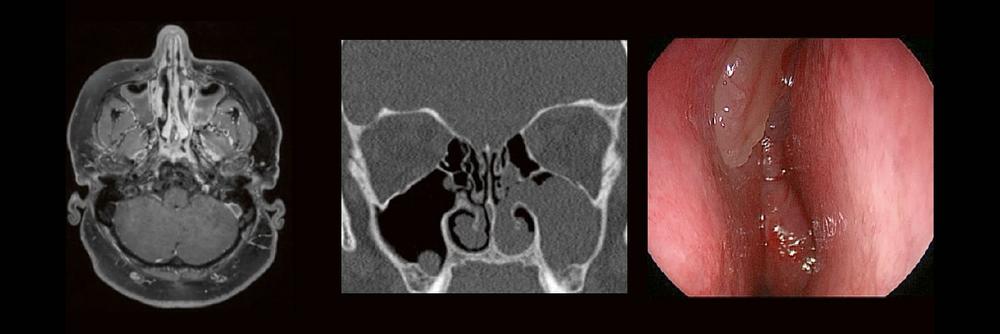

Dr. med. André ReisbergDr. med Sebastian Plößl Die bildgebende HNO-Diagnostik macht es Anfängern nicht leicht. Die Anatomie ist komplex und…